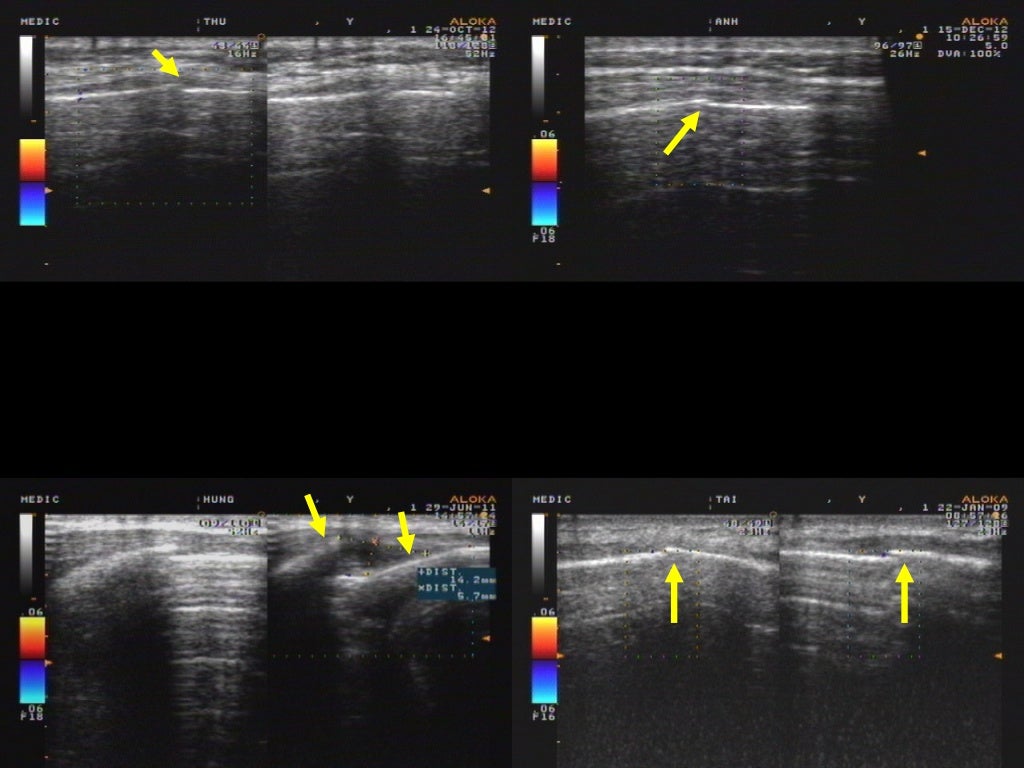

Ultrasonography of fractures in sports medicine British Journal of

a The picture shows a rib fracture with a cortical step (arrow Rib Fracture Ultrasound Half of the rib fractures are not. In this five minute sono, we provide a guide on using ultrasound to evaluate rib and sternal fractures. Rib fractures are the most common skeletal thoracic injuries resulting from blunt chest trauma. We go over probe choice,. Ct chest better sensitivity (63%) and specificity (97%) ultrasound. May only pick up 24% of fractures;. Rib Fracture Ultrasound.

Ultrasonography of fractures in sports medicine British Journal of Rib Fracture Ultrasound We go over probe choice,. Rib fractures are the most common skeletal thoracic injuries resulting from blunt chest trauma. In this five minute sono, we provide a guide on using ultrasound to evaluate rib and sternal fractures. Has been shown to detect rib fractures not seen on radiographs;. Once a rib fracture is diagnosed, ultrasonography can then be conveniently and. Rib Fracture Ultrasound.